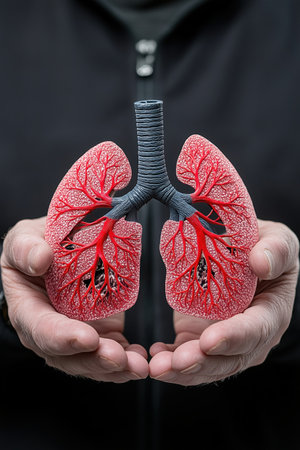

A close up of a human lung with red, blue and pink veins. The lung is shown in a 3D model, with the red veins representing the blood vessels that supply oxygen to the lung tissue

Delicate hands support a vivid anatomical model of human lungs, showing intricate details of the bronchi and blood vessels. The contrasting colors highlight the complexity of respiratory anatomy.

Hands holding anatomy lung, world tuberculosis tb day, world no tobacco day. generative ai